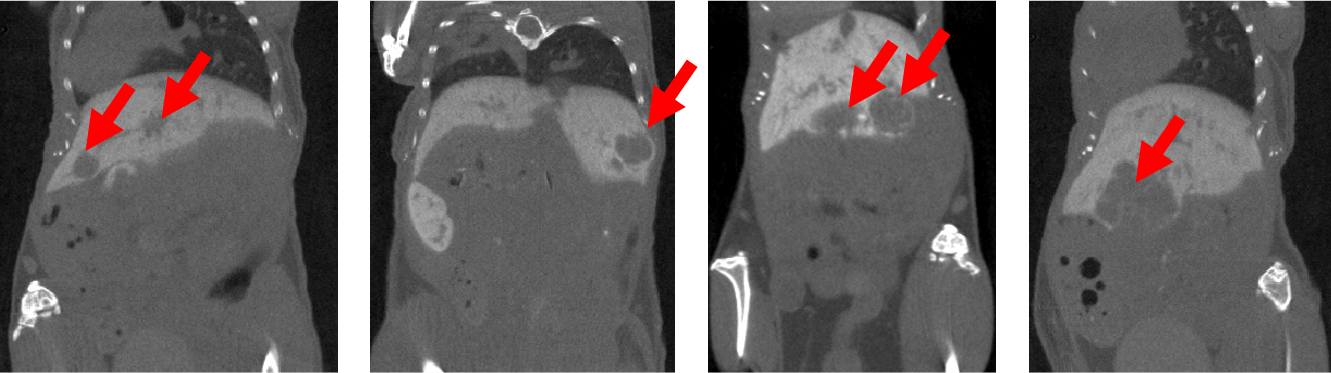

7、新冠肺炎CT成像

檢測活體敘利亞倉鼠的肺部CT影像:定性分析方法:根據(jù)CT影像進行病變程度評分;定量分析方法:通過分析像素密度在56-255范圍內(nèi)的圖像部分,定量分析CT影像上的不含氣肺體積(肺組織體積)(non-aerated lung volume);通過分析像素密度在0-55范圍內(nèi)的圖像部分,定量分析氣管(airways)和含氣肺體積(aerated lung volume)。影像表明:黃色箭頭表示肺實變,藍色箭頭表示支氣管擴張。

圖8. CT影像.png